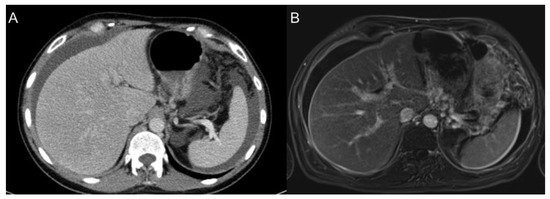

2.1. Computed Tomography (CT)

2.2. Magnetic Resonance Imaging (MRI)